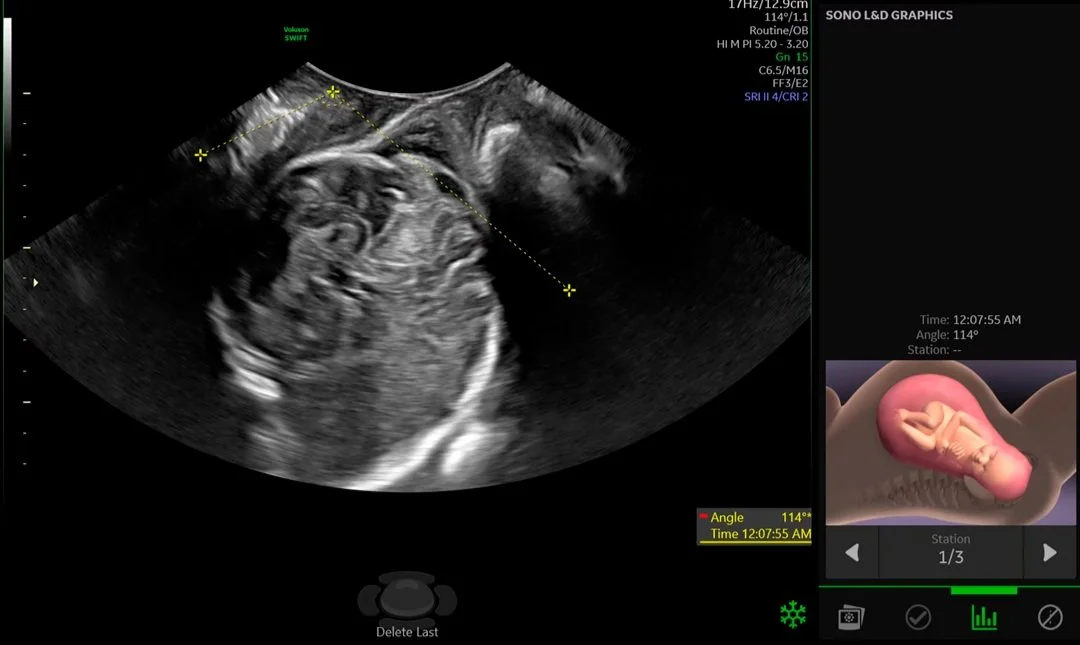

Obstetricia

Desde las primeras fases del embarazo hasta el nacimiento, la salud de la madre y el feto es su prioridad. Es por eso que nuestra prioridad es garantizar una adquisición de imágenes extraordinaria en todas las etapas del embarazo para explorar con confianza la anatomía del feto y detectar anomalías más rápida que nunca antes.

Diagnóstico pormenorizado

El proceso de parto está lleno de emoción, expectativas y, a veces, incertidumbre. Con imágenes extraordinarias y seguimiento innovador de la evolución del parto, Voluson SWIFT puede ayudarlo a controlar la progresión del parto, así como el bienestar tanto del bebé como de la madre, lo que lo ayuda a tomar decisiones clínicas más informadas.